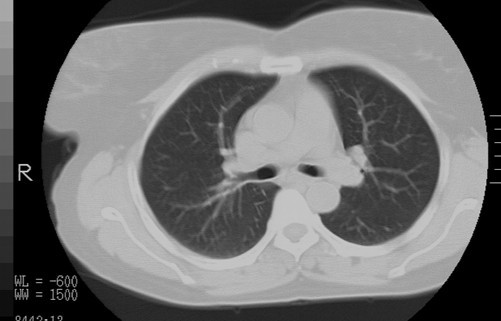

以下是引用随光逐影在2010-3-1 8:36:00的发言:[br]右上纵隔囊性占位性病变,考虑支气管囊肿,不排除神经源性肿瘤。